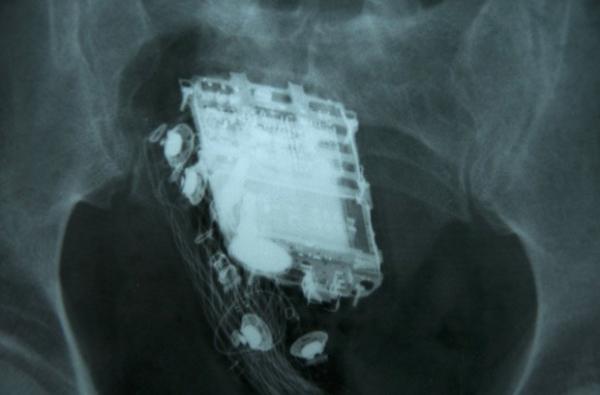

Raio-X mostra o telefone celular no reto de prisioneiro de 58 anos em Colombo, no Sri Lanka

Um prisioneiro do Sri Lanka que tentou esconder seu telefone celular durante uma inspeção em sua cela foi descoberto quando os guardas ouviram toques vindos de suas nádegas, informou um funcionário dos serviços médicos nesta sexta-feira (8).

O condenado de 58 anos de idade precisou ser internado no hospital nacional em Colombo, onde os médicos mais tarde retiraram o aparelho de seu reto.

O preso está cumprindo uma pena de 10 anos por roubo na prisão de segurança máxima de Welikada, na capital.

Ele disse que o homem permaneceu no hospital por dois dias, mas recebeu alta e foi enviado de volta para a prisão nesta sexta-feira, depois que o celular foi retirado.